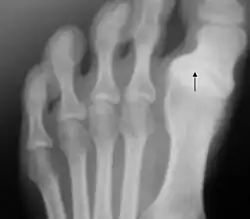

Radiographie d'un cas d'hallux varus.